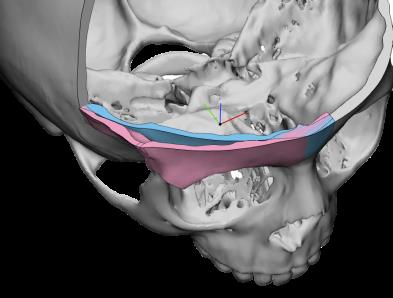

Chirurgia Oro-Mascellare per riabilitazioni protesiche post oncologiche

I pazienti che per motivi oncologici o per esito di osteonecrosi per uso di farmaci della categoria bifosfonati (in uso nelle gravi forme di osteoporosi o nel trattamento coadiuvante delle metastasi ossee)hanno subito gravi demolizioni dei mascellari e conseguente perdita della funzionalità masticatoria necessitano di ricostruzione e rifunzionalizzazione dell'apparato masticatorio con ricostruzione dell'osso mandibolare o del mascellare superiore attraverso innesti di osso , di lembi mucosi e/o muscolari di vicinanza ed a volte di implantologia preprotesica con impianti zigomatici , pterigoidei o convenzionali , tutto cio'con il fine di ripristinare una corretta funzione ma anche una auspicabile vita di relazione.

![]() | ![]() | ![]() | ![]() |

![]() | ![]() | ![]() |